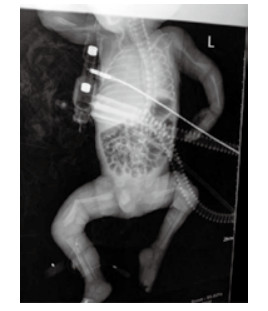

1 资料与方法孕妇20岁, 因“停经38周、阴道流液伴下腹坠胀1 h”于2015年9月10日23:45入住浙江大学明州医院产科。孕妇平素月经规律, 停经3个月在社区医院建卡定期产前检查, 停经17周产前筛查低风险, 停经20周自觉胎动无异常, 停经25周社区医院超声检查未见异常, 停经32周再次社区医院超声示胎儿臀先露, 羊水指数(AFI)22.5 cm, 余未见异常。既往体健, 无遗传病家族史, 孕期无病毒感染及放射线等不良接触史。入院查体:生命体征平稳, 发育正常, 营养可, 心肺听诊无异常; 腹膨隆, 宫高33 cm, 腹围99 cm, 胎位LSA, 胎心率140次/min, 先露臀、棘上3 cm, 宫口容1指, 羊水淡黄色。入院超声检查:宫内孕, 单活胎, 臀位, 双顶径9.3 cm, 股骨长7.4 cm, 头围33.4 cm, AFI 9.6 cm。因“臀先露”于9月11日02时09分剖宫产娩出一男活婴, 手术顺利, 重2 550 g, 身长50 cm, 面部外观未见异常, 四肢瘫软外翻、骨细小有骨擦感, 阴茎短小、睾丸未降, 1分钟Apgar评3分, 立即清理呼吸道、行气管插管气囊加压及呼吸机辅助呼吸等抢救, X线片示双侧股骨中下段明显成角, 左肱骨下段轻度成角, 右肱骨中下段不连续, 断端错位并轻度重叠移位(图 1)。新生儿抢救1 h后无效死亡。死亡原因:新生儿重度窒息, 新生儿骨软骨发育异常并多发性骨折, 死亡原因不明确申请尸检。

| 图 1 X线显示新生儿双侧股骨及左侧肱骨成交, 右侧肱骨骨折, 四肢骨及肋骨发育细小、骨密度减低 |

新生儿尸检报告:(1)成骨不全病(脆骨病); (2)双侧肱骨、双侧股骨病理性骨折; (3)双侧肘关节、腕关节、膝关节脱位, 桡、尺骨骨膜分离, 骨形态细小; (4)颅骨发育不全; (5)头皮帽状腱膜下出血; (6)心脏、大血管、双肺无畸形。

X线检查在成骨不全诊断方面有重要价值, 表现为骨密度降低、骨皮质变薄、四肢短特别是下肢多发性骨折, 对超声或临床评估不排除OI患儿可行辅助性诊断; 对有OI患病或生育史者再次妊娠可通过培养绒毛成纤维细胞分析胶原合成对成骨不全进行产前诊断[21]。COL1A1和COL1A2基因突变检测是最直接证实该病分子基础的方法, 但仅适用于孕前已明确先证者具体突变类型的孕妇[22]。

该病例产前检查一直在基层医院进行, 多次超声均无长骨短、弯曲、成角和骨折等异常, 孕晚期羊水增多但无进一步系统评估胎儿颅骨压缩程度及心胸比例, 剖宫产娩出后发现患儿身高四肢长度正常, 但四肢关节脱位且骨骼发育细小并有骨摩擦感, 1分钟Apgar评3分, 抢救过程中X线检查发现右肱骨骨折, 左肱骨及双侧股骨成角, 考虑到骨软骨发育不良疾病可能, 但持续抢救无效死亡, 尸检发现严重的颅骨发育不良、四肢病理性骨折并骨发育不良, 明确诊断OI, 但未行相关基因诊断。为产前漏诊的OI患者, 虽无短长骨, 但全身成骨不全严重, 初步考虑为重度或致死性OI, 具体分型不能确定。漏诊的原因首先考虑与“无短长骨”有关, 但基层医院综合诊治能力低也是重要因素。患儿父母表型正常, 故可能为COLlAl或COL1A2基因突变所致, 不能排除患儿父母为OI隐性基因携带者。OI患者的后代具有较高的OI发病风险, 但当先证者为散发病例时, 其父母再次生育患儿的风险较小。该患者再次妊娠咨询:散发OI, 发病率低, 且无基因诊断, 再次妊娠以全面系统的超声筛查为主, 必要时结合其他方法综合评估。